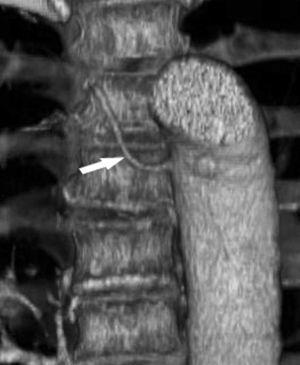

Pese a las conocidas limitaciones de la TC, ésta continúa siendo la técnica de elección en la estadificación del tumor en los pacientes con CPNM; su sensibilidad y especificidad en la determinación de la infiltración de pared oscilan entre el 38 y el 87% y del 40 al 90%, respectivamente, según las series. El desarrollo de nuevos equipos de TC helicoidal y principalmente las TC multidetectoras (TCMD) proporcionan unas imágenes 2D de mayor resolución con la posibilidad de hacer reconstrucciones multiplanares (MPR) en distintos planos del espacio e incluso 3D con la consiguiente mejora de la valoración del tumor, su extensión e infiltración de estructuras vecinas5 (fig. 4). Así, con la TCMD se puede poner de manifiesto con mayor fiabilidad la invasión de la cisura, la pared torácica o el mediastino, y además es capaz de determinar, gracias a las reconstrucciones de volumen, la relación exacta del tumor con la vía aérea (fig. 5). El progreso en la capacidad diagnóstica deriva del incremento en la resolución de las imágenes obtenidas y de la posibilidad de emplear nuevas aplicaciones como la broncoscopia virtual y la visualización en tiempo real. La broncoscopia virtual es útil para valorar la invasión del árbol traqueobronquial con la finalidad de planificar la cirugía, también como guía para el fibrobroncoscopista y, por último, porque permite ver el árbol bronquial distal a la estenosis (fig. 6)6. La capacidad de ver la imagen en tiempo real es especialmente útil cuando se emplea como guía en maniobras intervencionistas como biopsias percutáneas, ya sea con finalidad diagnóstica o como parte de la estadificación (fig. 7). Esta técnica de guía de biopsia denominada TC fluoroscopia reduce el número de pases y el tiempo global de la exploración, implica un menor riesgo de lesión de estructuras y permite la visualización inmediata de las posibles complicaciones7.

Fig. 6.--Broncoscopia virtual. (A) Reconstrucción coronal que muestra una masa hiliar derecha (T) con infiltración del ángulo traqueobronquial. (B) Visión endoscópica del tumor en la que se observa la infiltración de la tráquea y la relación con la carina (asterisco).